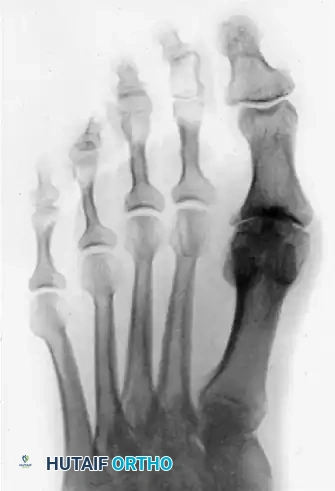

Salvage Procedures: First MTP Arthrodesis

If intraoperative assessment reveals that the articular cartilage destruction is far more severe than anticipated (Grade IV hallux rigidus), or if the joint remains grossly unstable or painful, the surgeon must be prepared to convert the cheilectomy to a first MTP arthrodesis. Arthrodesis provides definitive pain relief at the cost of joint motion.

Image

Postoperative anteroposterior radiograph demonstrating a solid first MTP arthrodesis using a dorsal plate and interfragmentary screw construct.

The success of an arthrodesis relies heavily on the precise positioning of the hallux. The toe must be positioned in approximately 10 to 15 degrees of valgus and 15 to 20 degrees of dorsiflexion relative to the first metatarsal to allow for normal toe-off during gait.